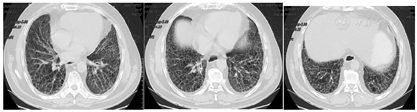

患者经治疗后肿瘤病灶明显缩小(图3,图4,图5,图6,图7,图8),定期于我院随访复查,目前一般情况良好,未见复发及远处转移。

PD-L1是一种跨膜糖蛋白,属于B7家族成员之一,一级结构包括290个氨基酸,亦由胞外区、疏水跨膜及尾部胞浆区组成[2]。有研究发现,PD-L1蛋白广泛表达于活化T淋巴细胞、巨噬细胞、B细胞等免疫细胞,还表达于多种类型的恶性肿瘤细胞表面,比如乳腺癌、胶质瘤、恶性黑色素瘤等[3]。PD-L1与其受体程序性死亡分子1 (PD-1)结合形成PD-1/PD-L1通路,该通路可介导形成机体的免疫抑制微环境,参与肿瘤细胞的免疫逃逸,继而促进肿瘤的发展。研究发现,27%~50%的肺癌患者可表达PD-L1[4,5],Koh等人[6]发现,在肺腺癌组织中PD-L1的阳性表达率为59%,且其阳性表达与患者淋巴结转移、组织分化程度及吸烟有关。有研究结果表明,肺鳞癌组织PD-L1阳性表达明显高于正常肺组织,PD-L1阳性表达与患者pTNM分期、淋巴转移有关,提示PD-L1在肺鳞癌的发生、进展过程中具有重要作用[3]。但目前单独研究PD-L1对肺鳞癌患者预后影响的报道甚少,尤其是伴有肺间质纤维化的肺鳞癌患者的相关研究更少,有待于大规模的临床试验。PD-L1抑制剂虽然可以达到预期的抗肿瘤效果,但这是一个非常复杂的过程,也有发生免疫相关不良事件的风险,包括诱发各种器官的炎症反应[7,8]。目前,其背后的机制仍不清楚,但先前的肺部疾病可能是免疫检查点抑制剂诱发肺炎的一个危险因素[9],所以由于肺炎的风险增加,肺间质纤维化合并肺癌患者接受免疫检查点抑制剂治疗的报道甚少。在以往的研究中,与传统非小细胞肺癌的化疗方案相比,抗PD-1治疗导致重度免疫相关性肺炎的发生率较高,但抗PD-L1治疗则不然[10]。也有研究显示,使用PD-1抑制剂患者3/4级免疫相关性肺炎的发生率仅略高于使用PD-L1抑制剂的患者[11]。此例病人为肺鳞状细胞癌伴肺间质纤维化,肿瘤细胞的PD-L1阳性表达百分比高达78%,因此在GP方案化疗的同时联合应用PD-L1抑制剂度伐利尤单抗,并在化疗与免疫联合治疗5疗程后以度伐利尤单抗单药维持。复查时可见右肺下叶的肿瘤病灶迅速且明显缩小,肺间质纤维化未见进展。患者治疗初期躯干部有散在皮疹出现,经抗过敏治疗后皮疹消失。患者1年半来复查病情稳定,未见复发及除淋巴结以外的其他部位转移,没有报告过除散在皮疹以外的免疫相关不良事件发生,也进一步证实了肺鳞癌病人化疗联合抗PD-L1药物作为一线治疗方案的可行性和安全性,为临床工作中肺鳞癌病人的治疗提供了新的思路。但目前病例数少,有待于大规模的临床试验。我们期望,在不远的未来,免疫治疗可使越来越多的肺癌患者获益。